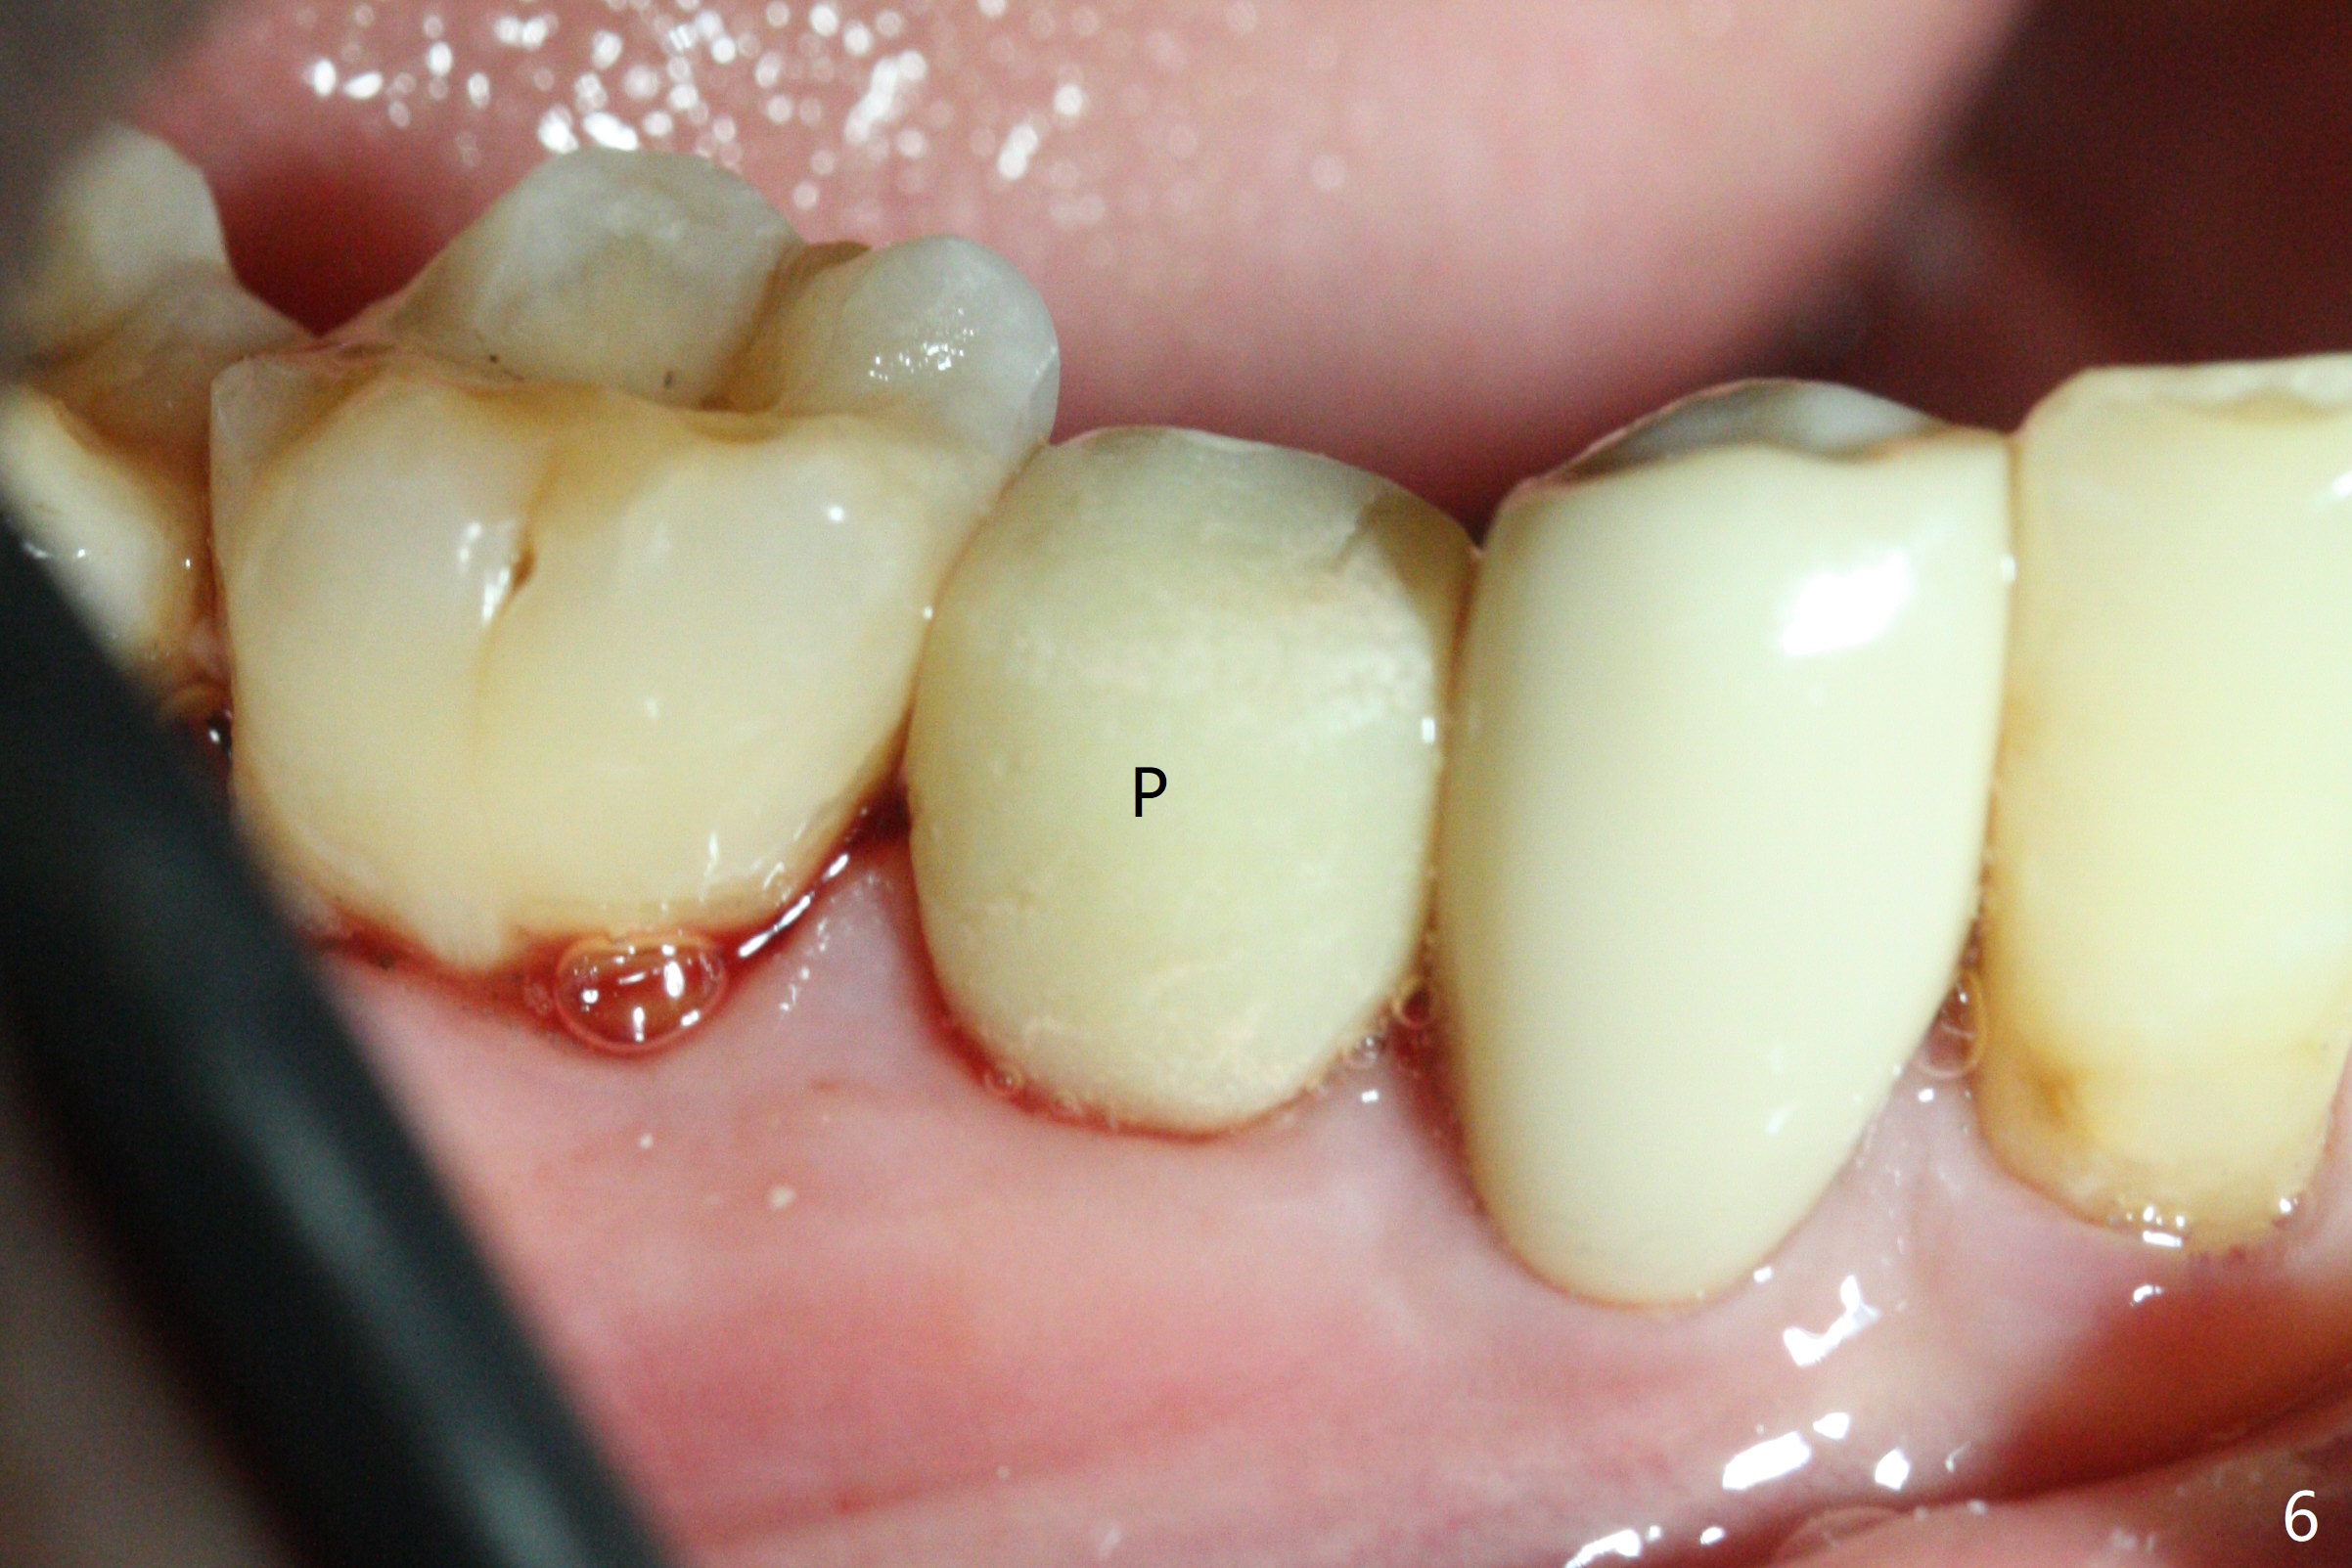

The tooth #29 is easily extracted with granulation tissue attached to the apex (Fig.1,2). The buccal plate is low. Initial osteotomy is established in the mesial slope of the socket for 13 mm subgingival (Fig.3 red dashed line). After adjustment of the osteotomy position and use of Magic Drills 2.8 and 3.3 mm for 15 mm subgingival, a 4x9 mm dummy implant is placed 2 mm subgingival (Fig.4). Final implant (Fig.5: 4x9 mm; red dashed line: socket) is placed 4 mm subgingival (supracrestal buccal; infracrestal lingual); Vanilla graft placed buccodistal (*). With placement of a 4.5x5.7(4) mm abutment (Fig.5), an infraocclusal immediate provisional (Fig.6 P) is fabricated to maintain the interdental papillae. One month later, the abutment dislodges. The patient insists upon no provisional so that he can masticate on the right side, since there is no functional molars on the left side. The implant appears to have osteointegrated 5 months postop (Fig7). The crown is loose 2.5 months post cementation (8.5 months postop); there is bone loss around the implant (Fig.8 *). Vanilla graft is placed after implant removal (Fig.9); in fact the neighboring teeth also have mobility (including periapical radiolucency at #30 (Fig.9 *)).